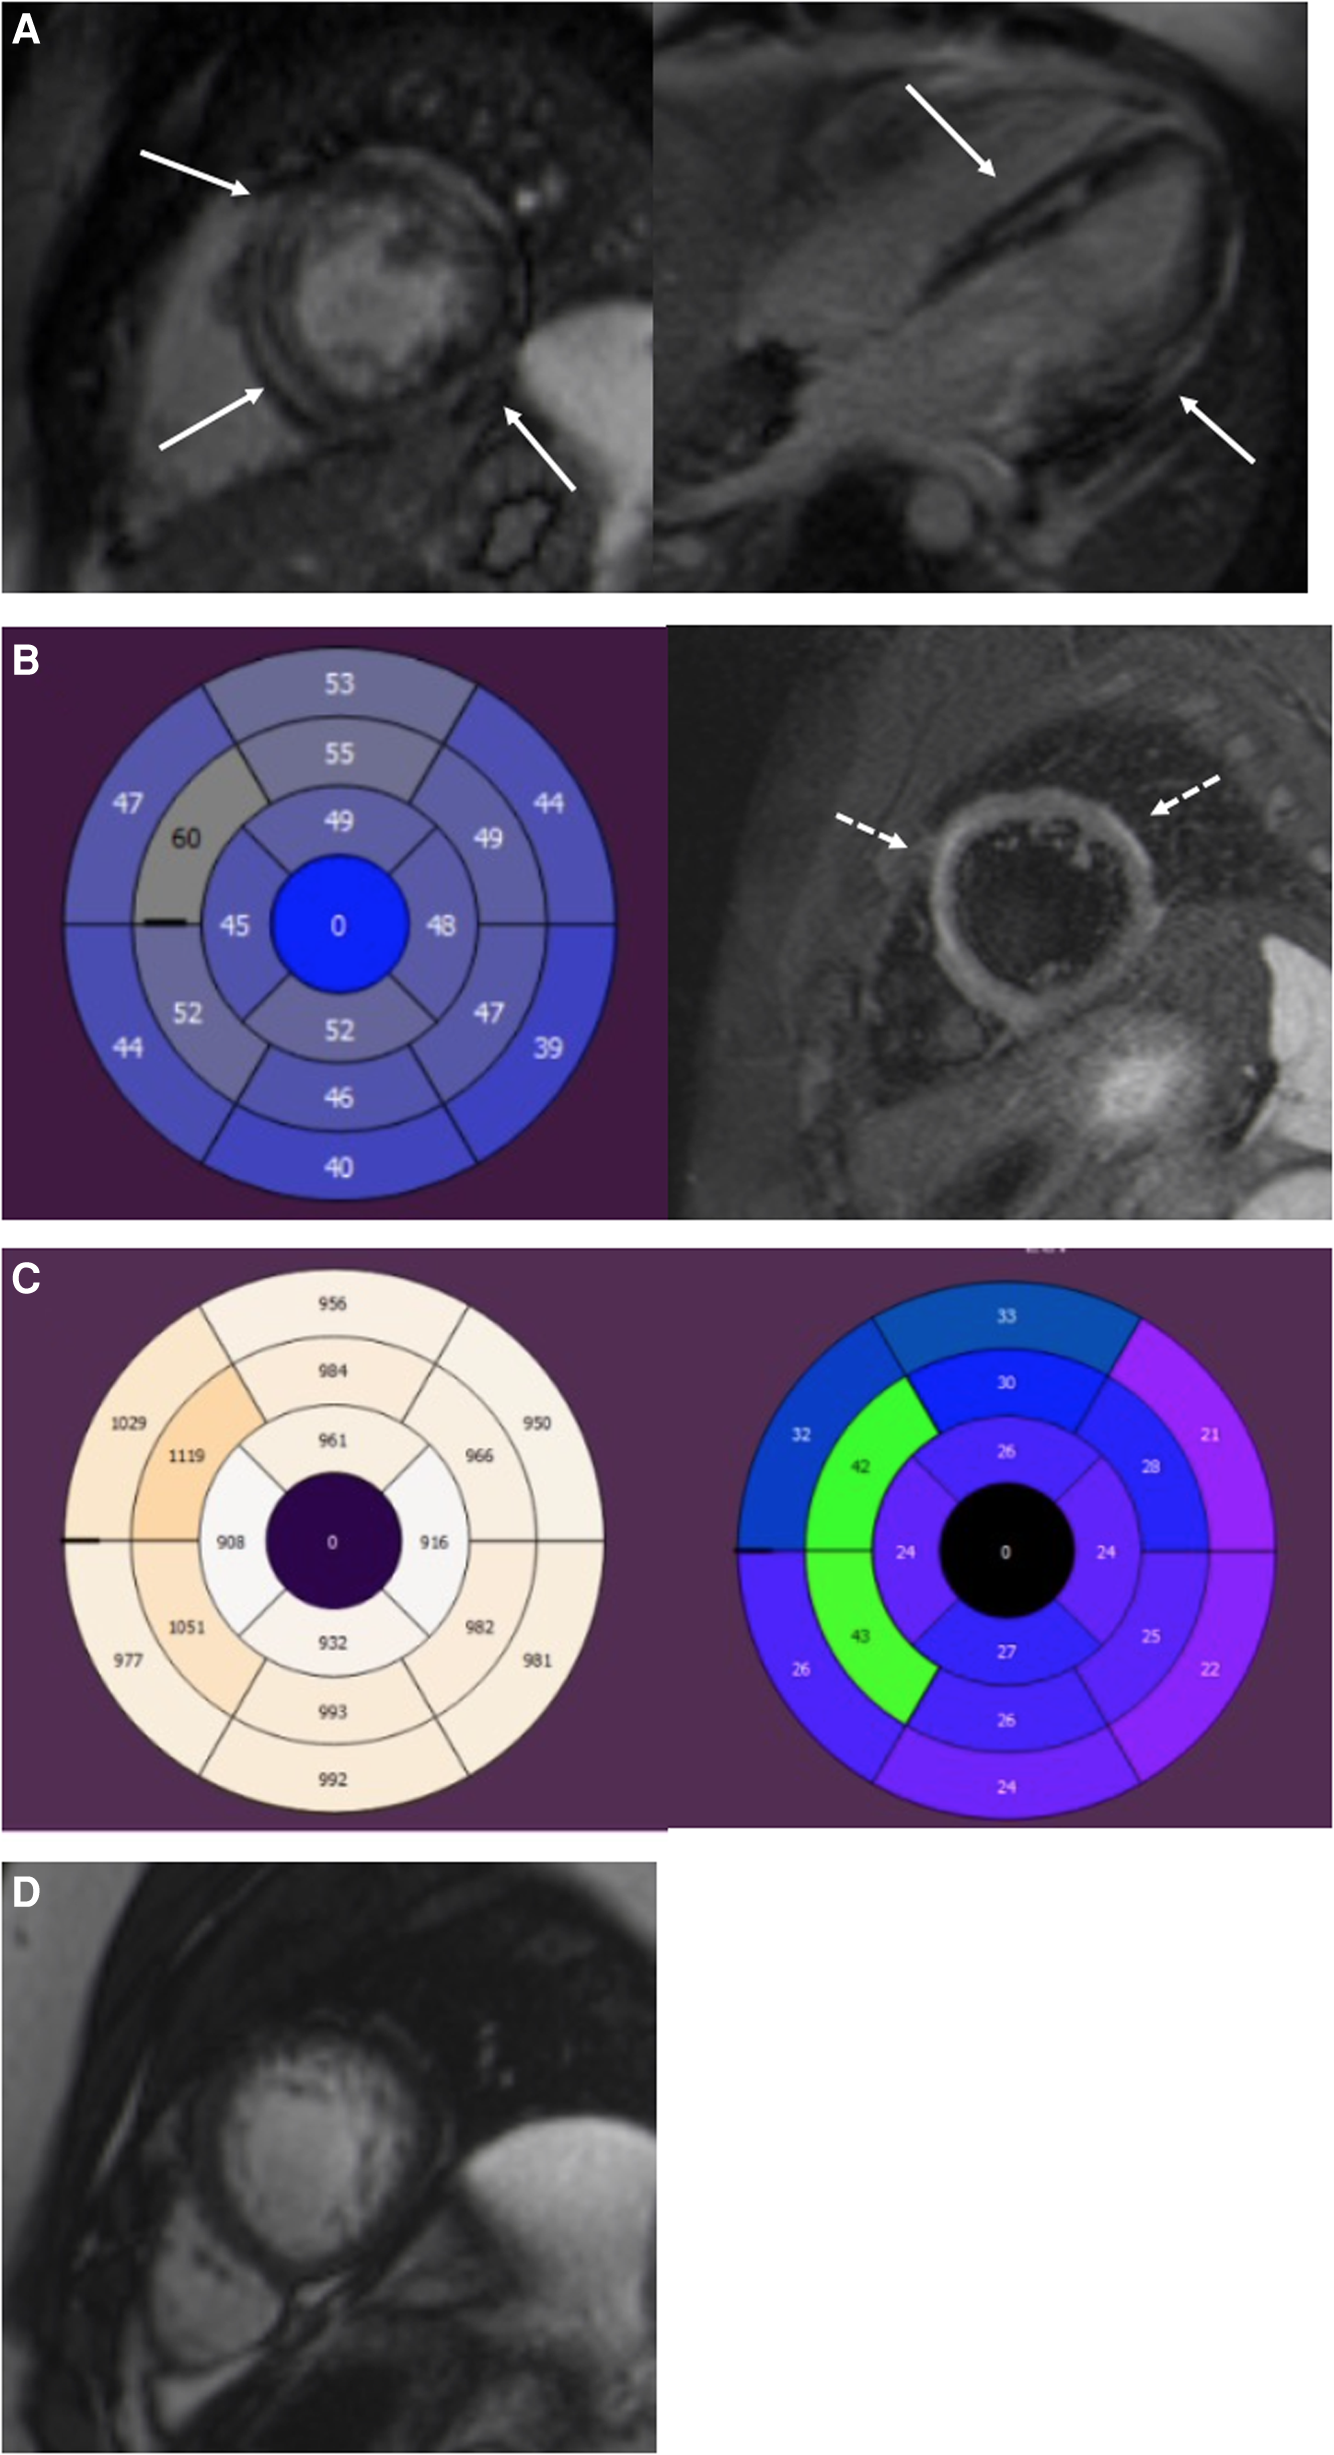

Figure 2

A 19-year-old male with DSP cardiomyopathy. (A) Short-axis and four-chamber LGE images show a midmyocardial and subepicardial ring-like enhancement of the LV (arrows). (B) AHA 17 segment Bull's eye of the LV. T2-mapping shows elevated T2 relaxation times (>52ā ms) in the anteroseptal and anterior segments referring to myocardial edema. T2 fs image with myocardial edema in the anterior septum and anterolateral wall (dotted arrows). Edema appears as a high signal intensity. (C) T1 mapping bulls eye figure with high T1 relaxation times (>1,000ā ms) in the anteroseptal segments of the LV. ECV is expanded in the same segments (>30%). (D) Short-axis cine image of the LV apex. Increased trabeculation of the apex but not fulfilling the LVNC criteria (>2.3). The ratio of the end-diastolic thickness of the non-compacted and compacted myocardial layers was 2.2. LGE, late gadolinium enhancement; LV, left ventricular; ECV, extracellular volume; LVNC, left-ventricular non-compaction cardiomyopathy.